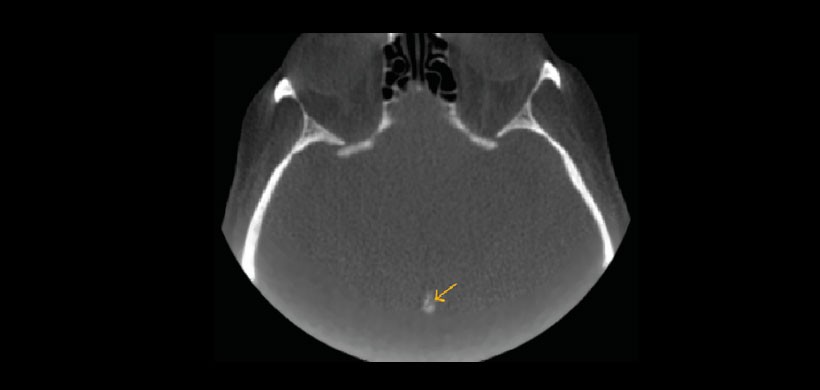

Fig 2. Tomografía volumétrica, vista axial. Muestra calcificación intracraneal a nivel de la glándula pineal.